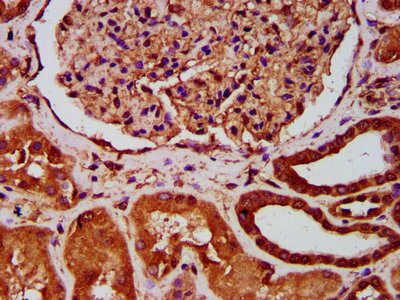

IHC image of CSB-PA002468LA01HU diluted at 1:400 and staining in paraffin-embedded human kidney tissue performed on a Leica BondTM system. After dewaxing and hydration, antigen retrieval was mediated by high pressure in a citrate buffer (pH 6.0). Section was blocked with 10% normal goat serum 30min at RT. Then primary antibody (1% BSA) was incubated at 4°C overnight. The primary is detected by a biotinylated secondary antibody and visualized using an HRP conjugated SP system.